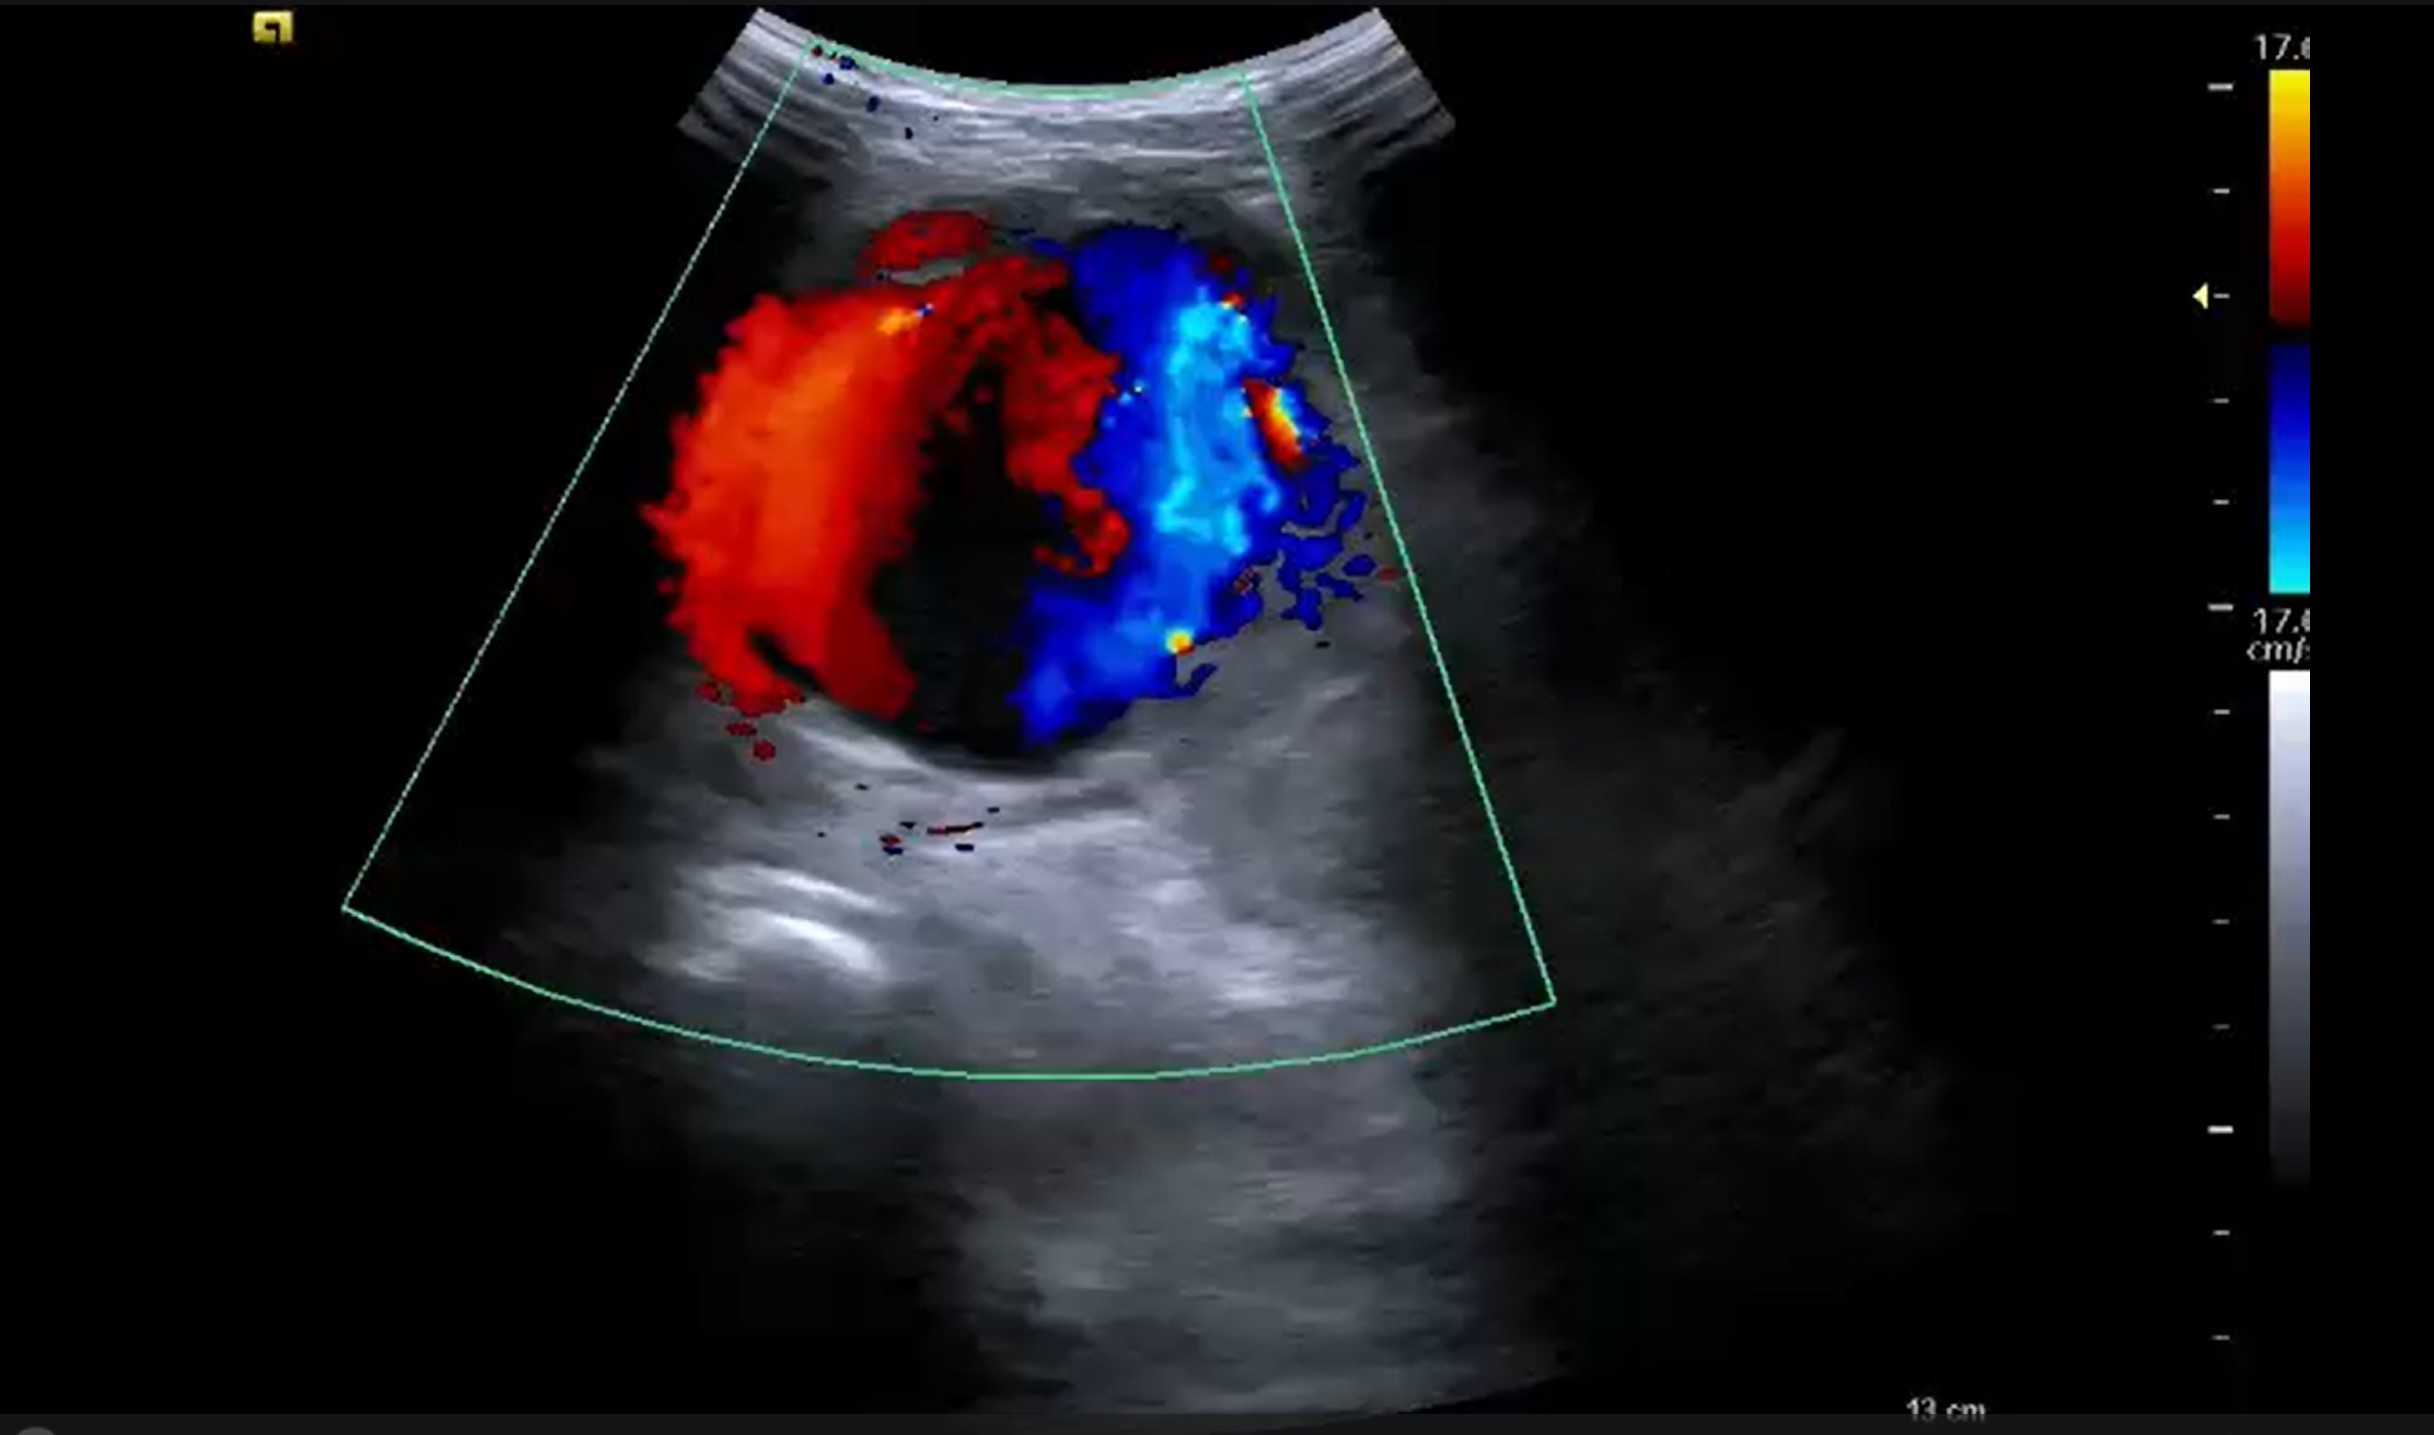

La arteria ciática persistente constituye una malformación vascular congénita excepcional, caracterizada por la permanencia anómala de este vaso embrionario que en condiciones normales involuciona para dar paso al desarrollo definitivo de la arteria femoral. Su interés radica en que presenta una marcada predisposición a desarrollar aneurismas, lo que le atribuye una importante relevancia clínica pese a su baja prevalencia. El diagnóstico puede facilitarse mediante el uso de la ecografía, ya que el signo del Yin-Yang en Eco-Doppler es un hallazgo característico.